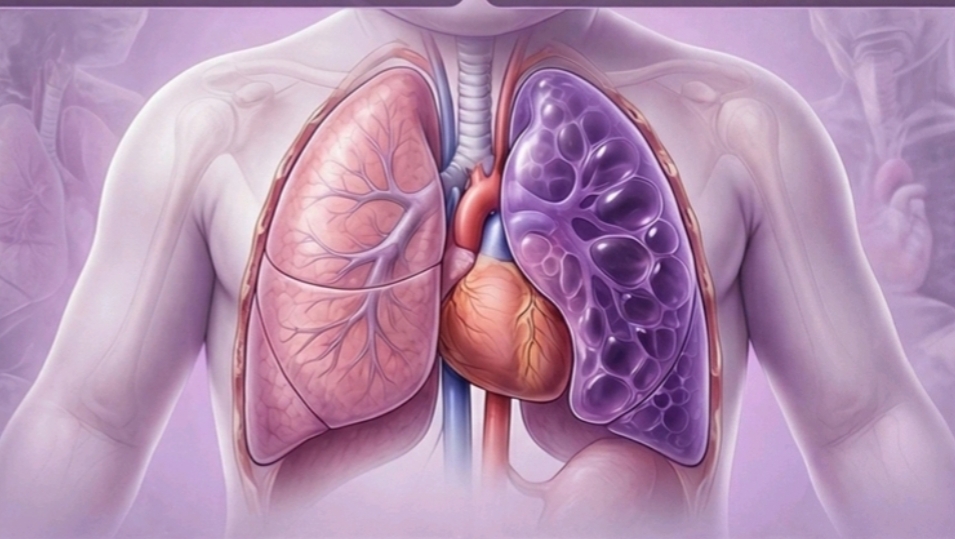

- Photorealistic Infographics of Various Causes of Neonatal Respiratory Distress. Free preview

Congenital Pulmonary Airway Malformation (CPAM) & Bronchopulmonary Sequestration (BPS)

Congenital Lobar Emphysema(CLE)

Detailed chapters on EA+TEF, CDH, CLH, CPAM & BPS, and Posterior Choanal atresia for in-depth understanding.